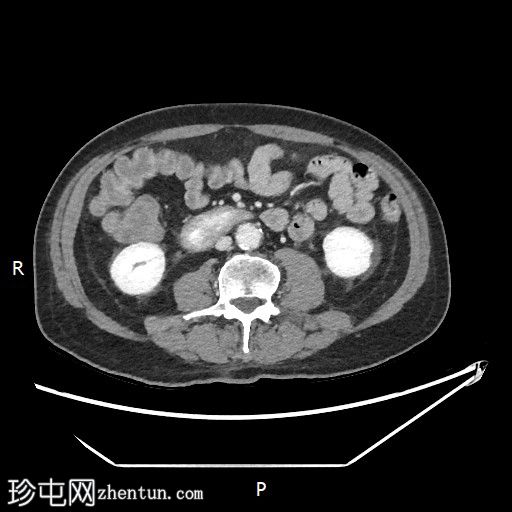

CT

轴位

平扫

1.jpg

轴位增强扫描

动脉期

2.jpg

胃内出血

造影剂外渗提示十二指肠第二段活动性出血

6.jpeg

十二指肠第三段造影剂积聚

活动性出血

7.jpeg